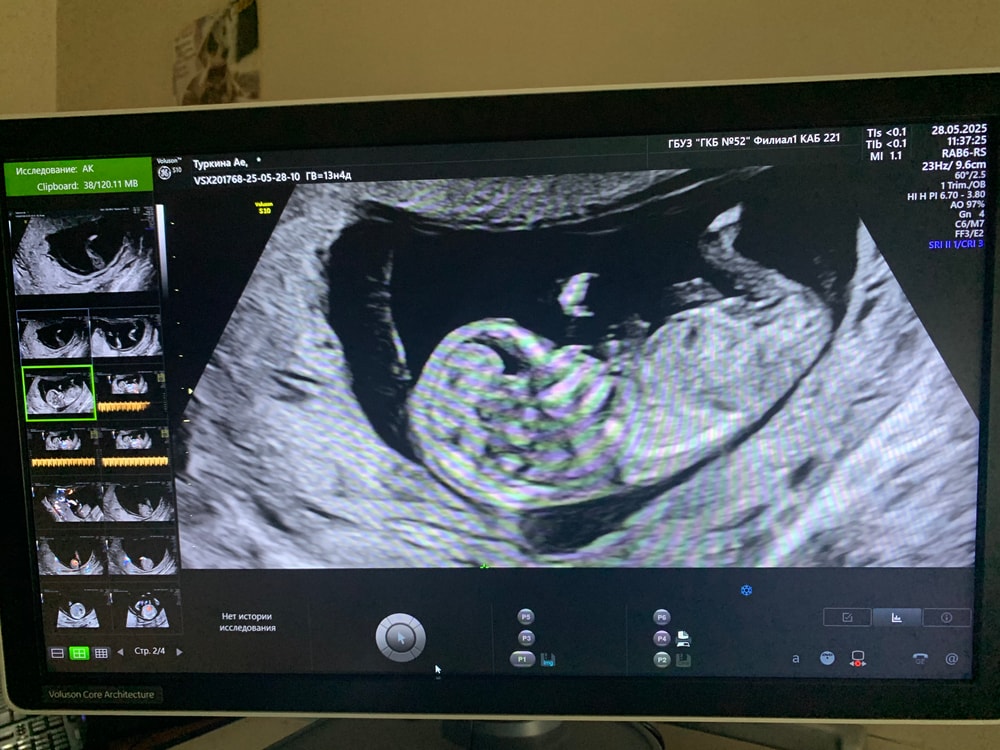

здесь не видно полового бугорка

Ножкой закрыл всё, не видно.

50/50 😂 Не видно бугорка

Это какой срок хоть

Наталья, 12 и 2